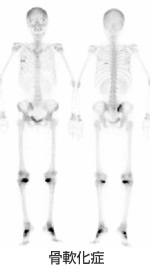

右の写真は「Cushing症候群」の画像です。